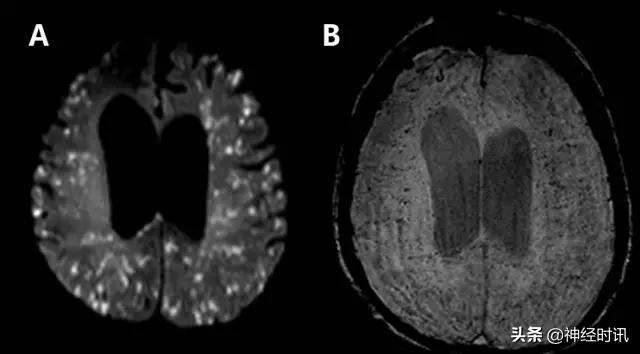

图20 一例21岁女性复发-缓解型MS患者,17岁时为评估其轻微脑震荡综合征而进行的首次MRI检查偶然发现多发性硬化。其表现为:幕上存在以特征性模式分布的多发性T2高信号病灶(C:FLAIR),且右额叶白质存在一个弥散受限病变(A:DWI,B:ADC)。

图21 一例70岁老年男性,患有糖尿病、非缺血性心肌病,且左室辅助装置并发了真菌性脓肿。MRI显示其左侧枕叶存在一个不规则的边缘薄层增强病变(D:T1WI增强),伴有弥散受限(B:DWI,C:ADC)、磁化率效应环(E:SWI)和周围的T2高信号改变(A:FLAIR)。